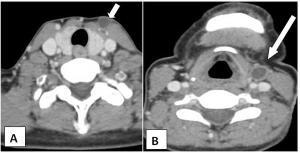

Case History: 75-year-old male presents with complaint of mucus discharge from external opening on skin at anterior aspect of mid part of neck on the left side.

Published: September 2nd 2014 | Updated: